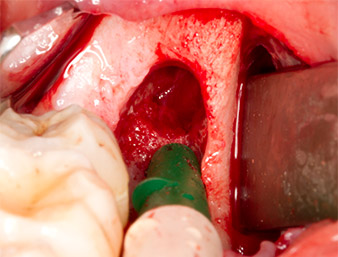

Using an instrument for periodontal debridement (Piezomed P1), the periodontal ligament space of the radix relicta was then widened minimally (Fig. 8).

The same activated instrument was inserted into the root canal and loosened the fragment as a result of its micro-oscillating vibrations (Fig. 9, 10).

Piezomed P1

Fig. 9: The Piezomed P1 instrument is recommended by the manufacturer primarily for periodontal debridement but is also suitable for surgical purposes. Here it is placed in the root canal after minimal widening of the periodontal ligament space.

Fig. 10: Due to its slender shape, the instrument can penetrate the root canal and remove the root remnant by means of micro-oscillation (vibration).

It was then possible to remove the approximately six-millimetre-long root remnant in one piece with the P1 attachment (Fig. 11).

Periapical inflamed tissue was also removed very carefully with a manual excavator. Fig. 12 shows the empty alveole with exposed inferior alveolar nerve.